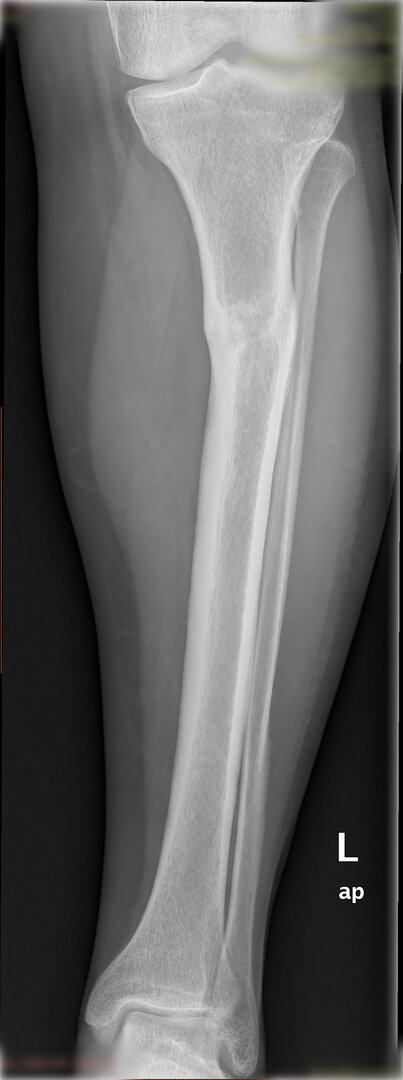

Ameliyat öncesi deformitenin iyi analiz edilmesi, planlamanın ona göre yapılması gerekir. Deformite düzeltilmesi esnasında eğer kısalık var ise sıra ile iki problemin de aynı anda düzeltilmesi mümkündür.

Diğer bir yöntem akut olarak düzeltme yöntemidir. Bu yöntemde kemiğe uygulanılan tespit yöntemi plak-vida kombinasyonu olabileceği gibi bir intramedüller çivi de olabilir.

Bu ameliyat öncesi bir deformite analizi yapılıp hangi kemikte, normalden ne kadar sapma olduğu tespit edilir. Daha sonra bu kemiğe yine ostetomi yapılarak bu anormal sapma düzeltilir.  Bu düzeltme plak-vida veya intramedüller çivi ile akut olarak düzeltilebileceği gibi bilgisayar destekli sirküler eksternal fiksatör ile tedrici olarak ta yapılabilir. Hangi yöntemin hangi hasta için uygun olacağına hasta özelinde karar veriyoruz, ne tür cerrahi tedavi olması gerektiğini danışabilirsiniz.